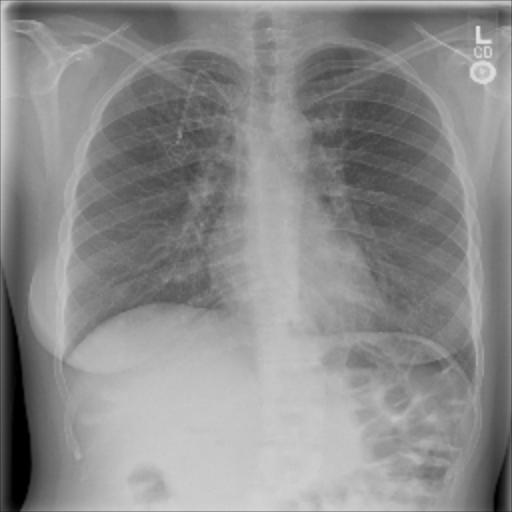

The data used in the following experiments consists of DICOM X-ray images, obtained from the University of Washington Medical Center and affiliated institutions, centered in Seattle by scanning radiology reports from the last three years. Inclusion criteria were: (i) Digital Radiography (DR) images, (ii) Chest radiographs, (iii) Posterior-anterior or anterior-posterior view position, (iv) Adult patients. Any personal health information was removed. Image-level labels were derived from natural-language processing based analysis of the reports. Cases were partially reviewed by a radiologist to confirm appropriate finding in the report’s impression section and this represented a critical finding. The resulting dataset contained 1003 images: 437 with pneumothorax, 566 with a different or no abnormality detected. We generated pixel-level annotations of the pneumothorax region for 305 of the positive cases. For training and evaluation, we divided the dataset into five cross-validation splits of similar size, such that images of the same patient resided in the same split.

The pre-trained ResNet-50 was also employed as the patch-level classifier within the MIL approach. We chose the binary cross-entropy between the maximum patch score and the image-level label as the loss function. The batch size was selected as the number of patches per image. We trained with an initial LR of for 30 epochs and achieved an average AUC of 0.930.01 using this method. High patch scores (indicated by thicker red frames, cf. Fig. 5(c)) give a hint on the location of the pneumothorax.

As pixel-level ground truth annotations were available only for a subset of the images, 871 images in total were used for training the FCN for 400 epochs. As a loss function, a weighted cross entropy (25.0 for pneumothorax pixels and 0.5 for non-pneumothorax pixels in order to account for the smaller size of pneumothorax regions) was employed at pixel-level with an initial LR of . With an average AUC of 0.920.02, the overall performance of this method is worse than the CNN and MIL. On the other hand, the FCN generates pixel-level probabilities (cf. Fig. 5(d)), which indicate the location of the pneumothorax. The average Dice coefficient for positively classified cases is .